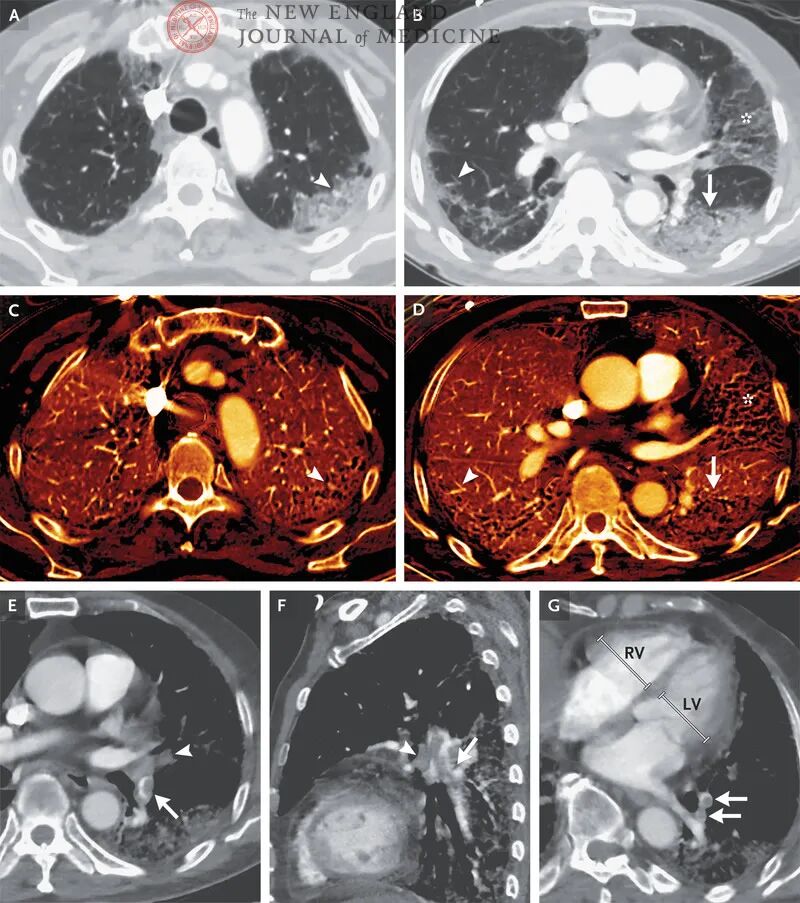

第二项诊断性检查是CT双能量成像(图3),扫描结果显示双肺外周多发磨玻璃样影,并可见肺间质增厚,左肺较右肺严重。部分磨玻璃影周围有实变影。增强相显示血液灌注降低,但与磨玻璃影密度不相称。左下叶动脉和段动脉可见不完全充盈缺损,环状动脉可见血栓闭塞。右心室与左心室大小之比约为1.1。

图3. 胸部CT